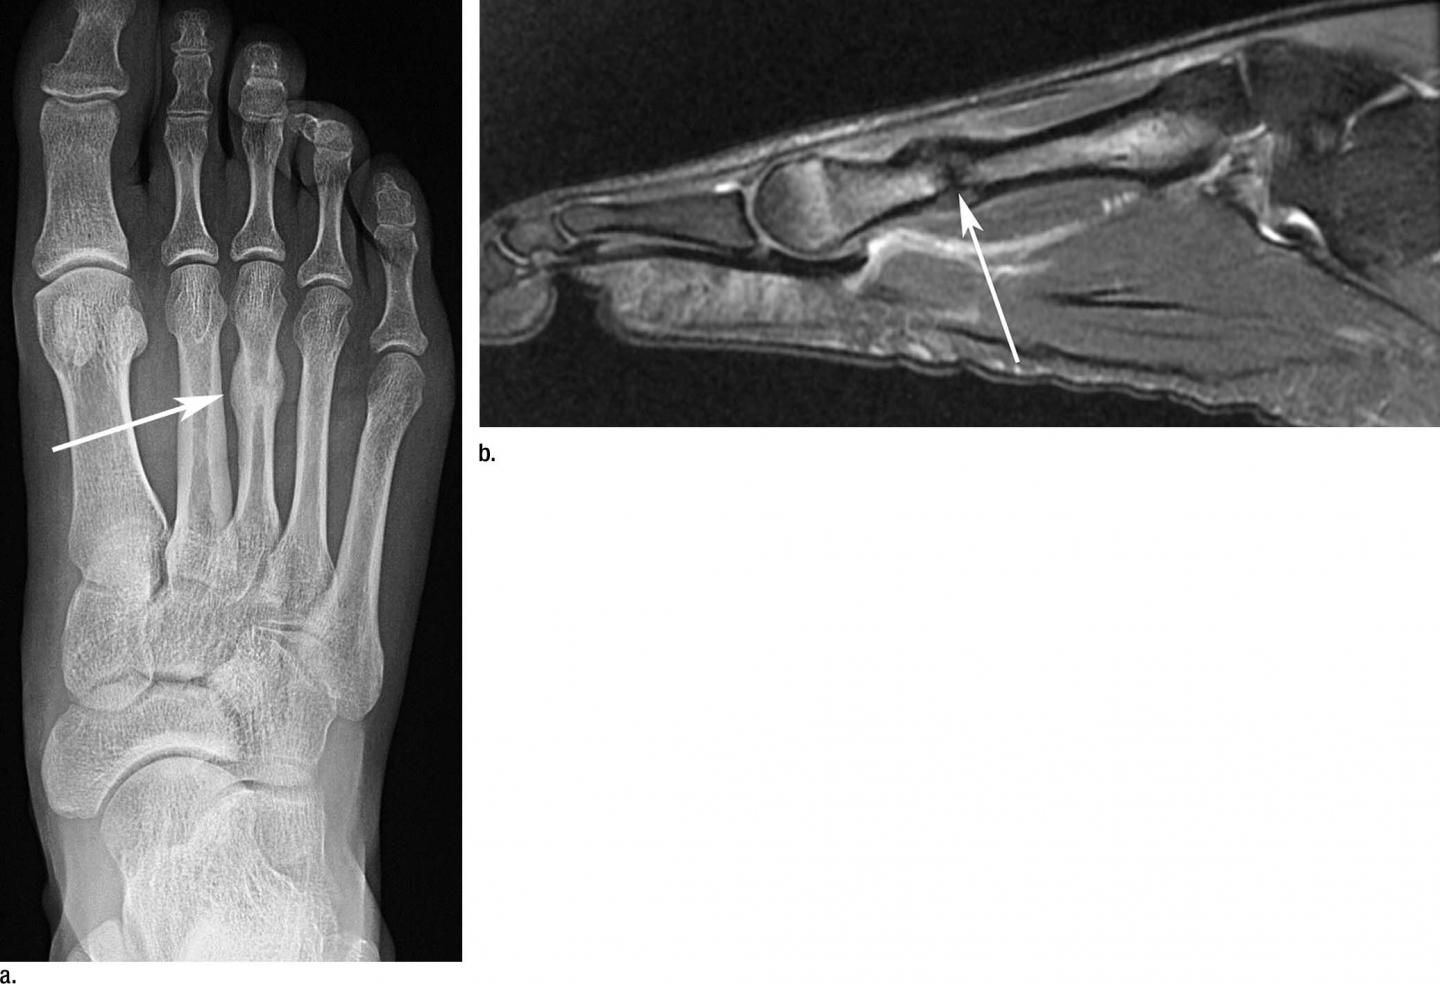

Dr. Guermazi and colleagues set out to describe the occurrence of imaging-depicted sports-related stress injuries, fractures, and muscle and tendon disorders, and to document the usage of imaging with X-ray, ultrasound and MRI.

The lower limb was the most common location of imaging-depicted sports-related injuries overall, and imaging of lower extremities was the most common exam. The second most common location was the upper limb.

Among muscle injuries, 83.9 percent affected muscles from the lower extremities. The sports most prone to muscle injuries were athletics, soccer (football) and weightlifting. Athletics also accounted for 34.6 percent of all tendon injuries.

Eighty-four percent of stress injuries were seen in the lower extremities. Stress injuries were most commonly seen in athletics, volleyball, artistic gymnastics and fencing. Fractures were most commonly found in athletics, hockey and cycling. Nearly half were upper extremity fractures.